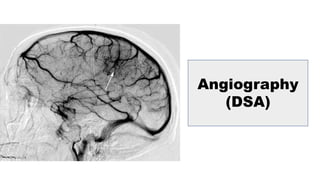

INVESTIGATIONS

Angiography

Magnetic resonance

Transcranial Doppler ultrasound

Diagnostic evaluation

CT

MRI

(DSA)

• CT

• MRI

• Visual examination

• Computed tomography angiography

• Four-vessel angiogram with selective external carotid artery (ECA)

injection remains the - gold standard